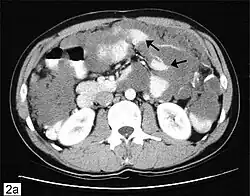

Ovarian cancer can also be a secondary cancer, the result of metastasis from a primary cancer elsewhere in the body.[26] About 5–30% of ovarian cancers are due to metastases, while the rest are primary cancers.[80] Common primary cancers are breast cancer, colon cancer, appendiceal cancer, and stomach cancer (primary gastric cancers that metastasize to the ovary are called Krukenberg tumors).[26] Krukenberg tumors have signet ring cells and mucinous cells.[29] Endometrial cancer and lymphomas can also metastasize to the ovary.[81]